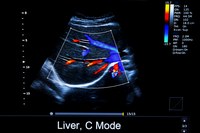

The Vevo F2 LT Imaging System (Fujifilm) is a high-performance imaging platform offering exceptional versatility across a wide range of preclinical applications. It is equipped wirh the 57 MHz probe, enabling low to ultra-high-resolution imaging of small animal models, particularly rodents.

• · Cardiology and vascular studies: heart function, vascular anatomy, and blood flow dynamics.